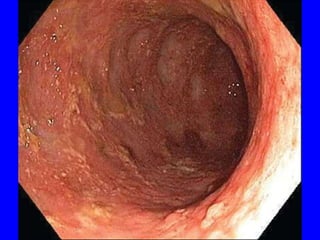

• Mild UC is characterized by mucosal edema, erythema& loss of the

normal vascular pattern.

• More significant disease produces granularity, friability, ulceration&

bleeding.

• Endoscopic findings vary from superficial aphthous ulcers to

discrete, deep ulcers that can be linear, stellate, or serpiginous &

that may coalesce into a “cobblestone” appearance

• Rectal sparing is typical, as are areas of inflammation separated by

normal mucosa (known as skip lesions).